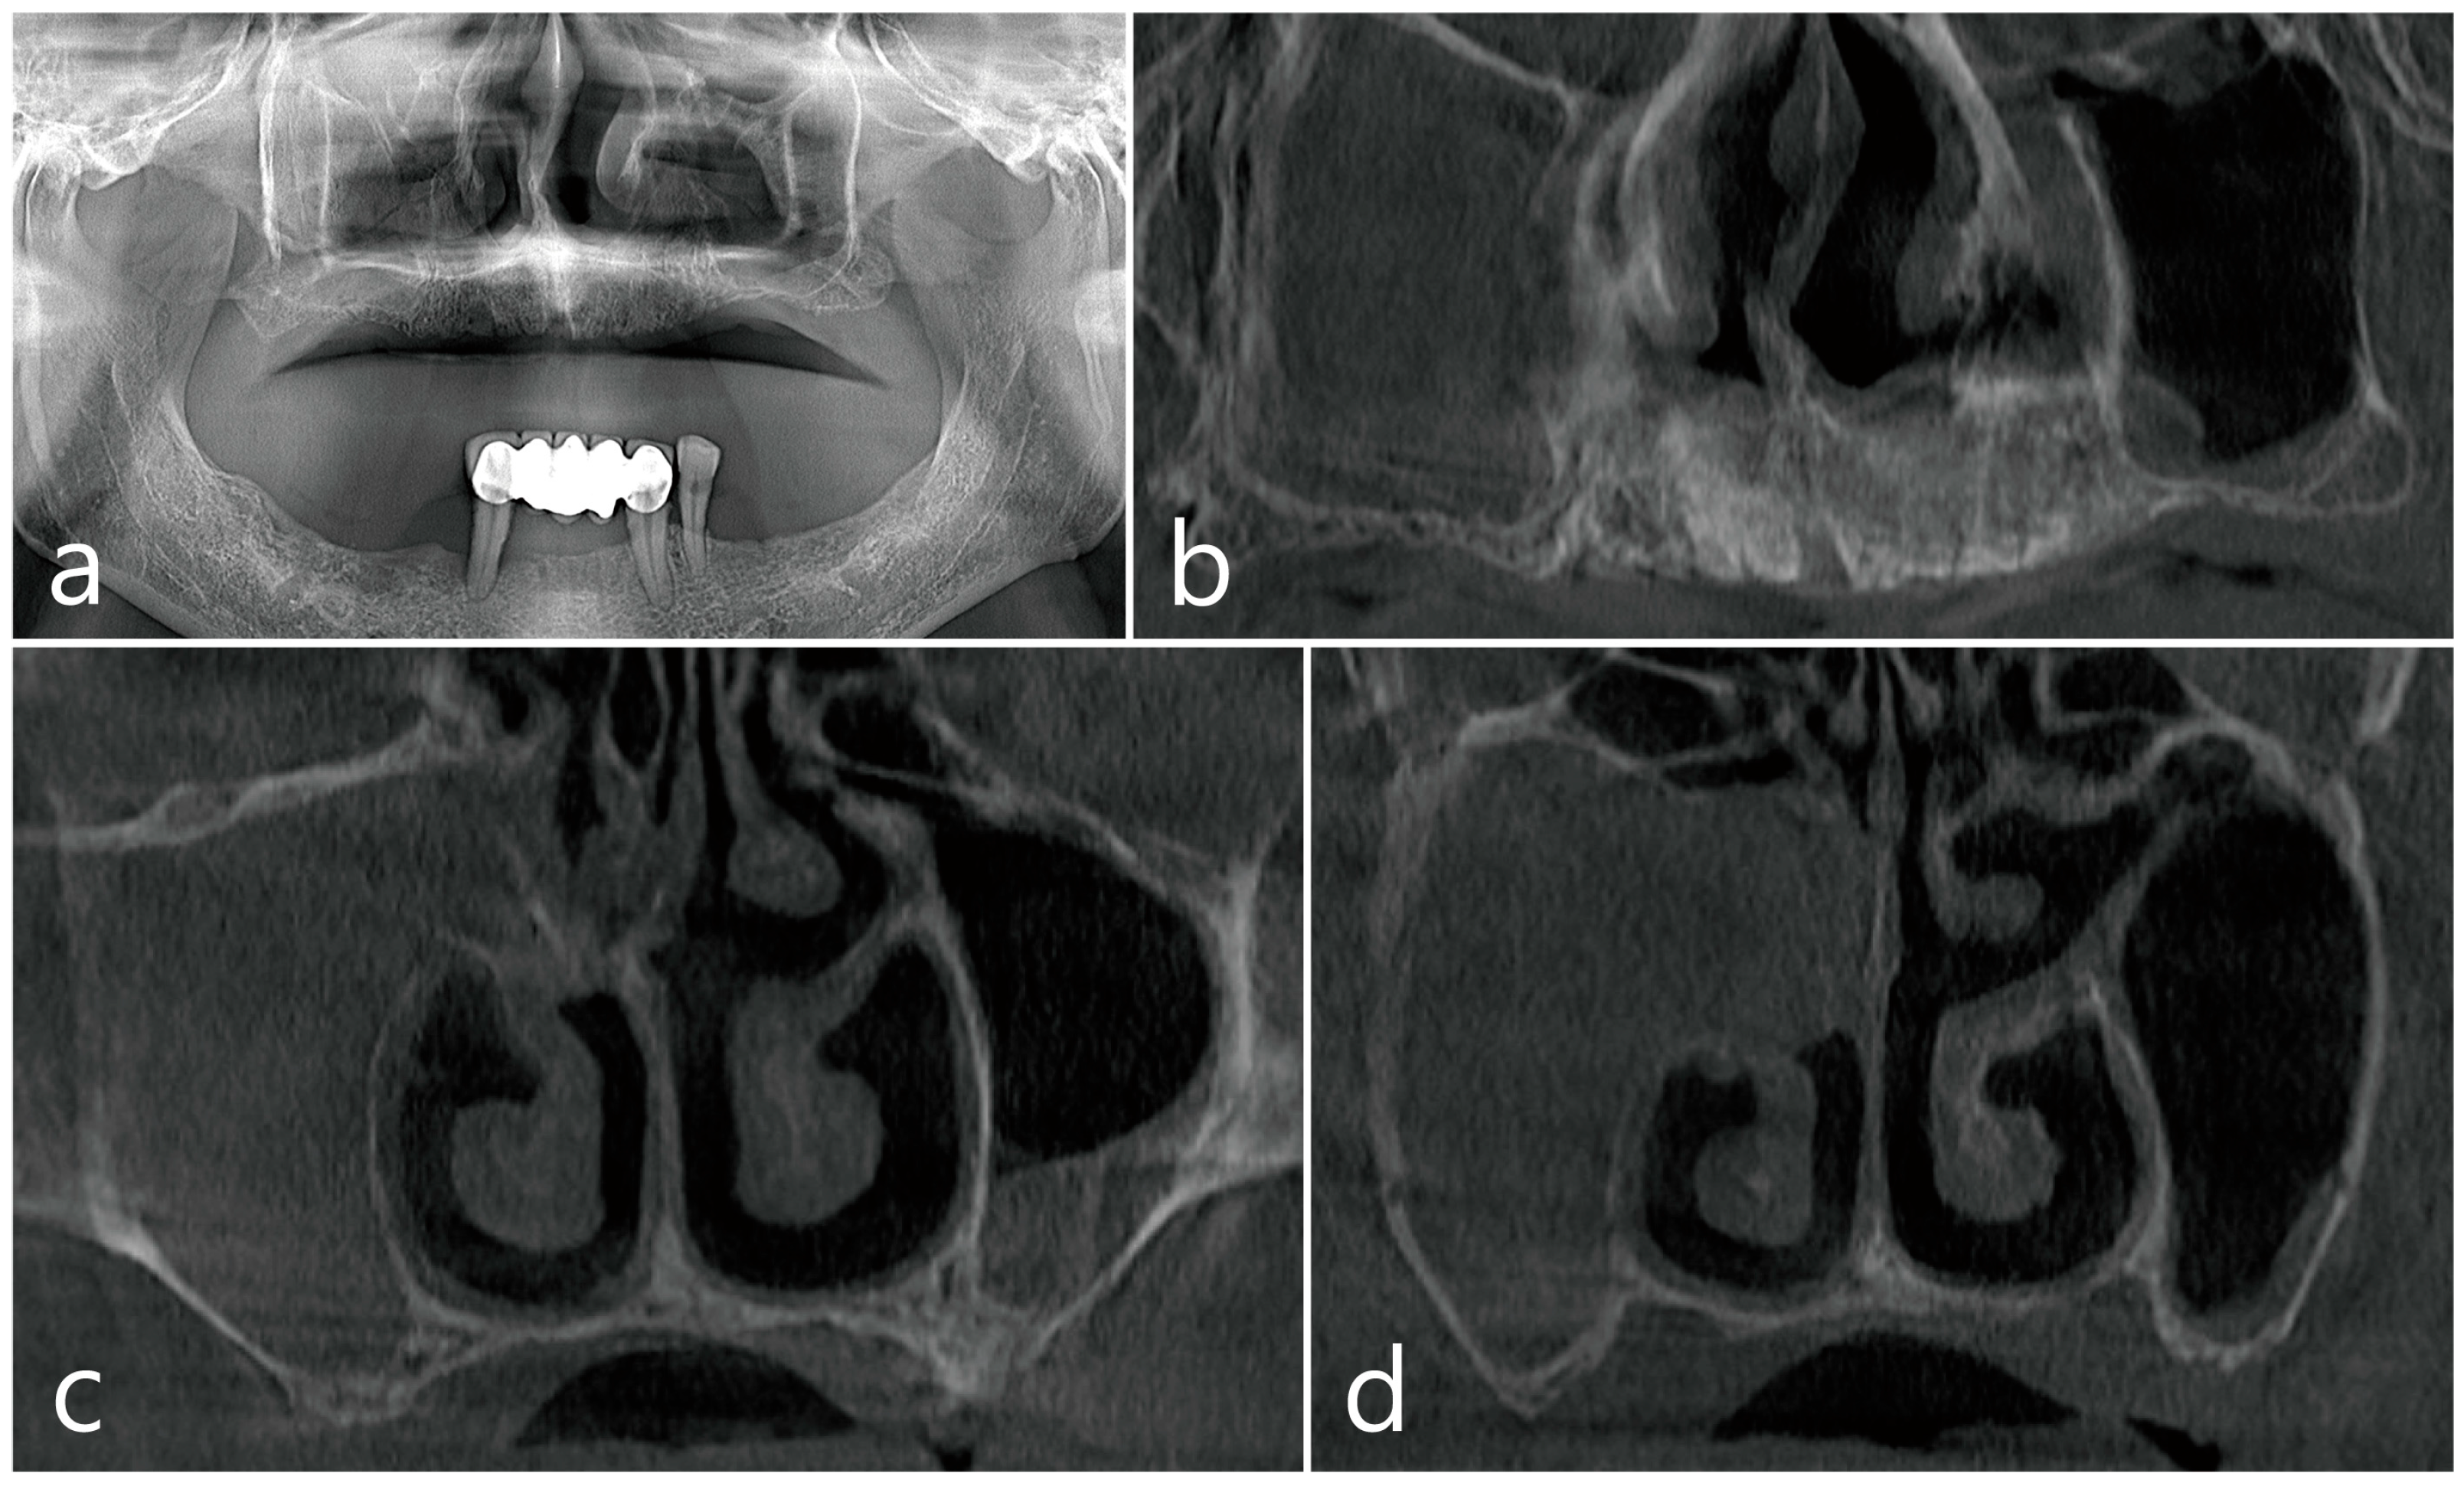

2.1. Case 1